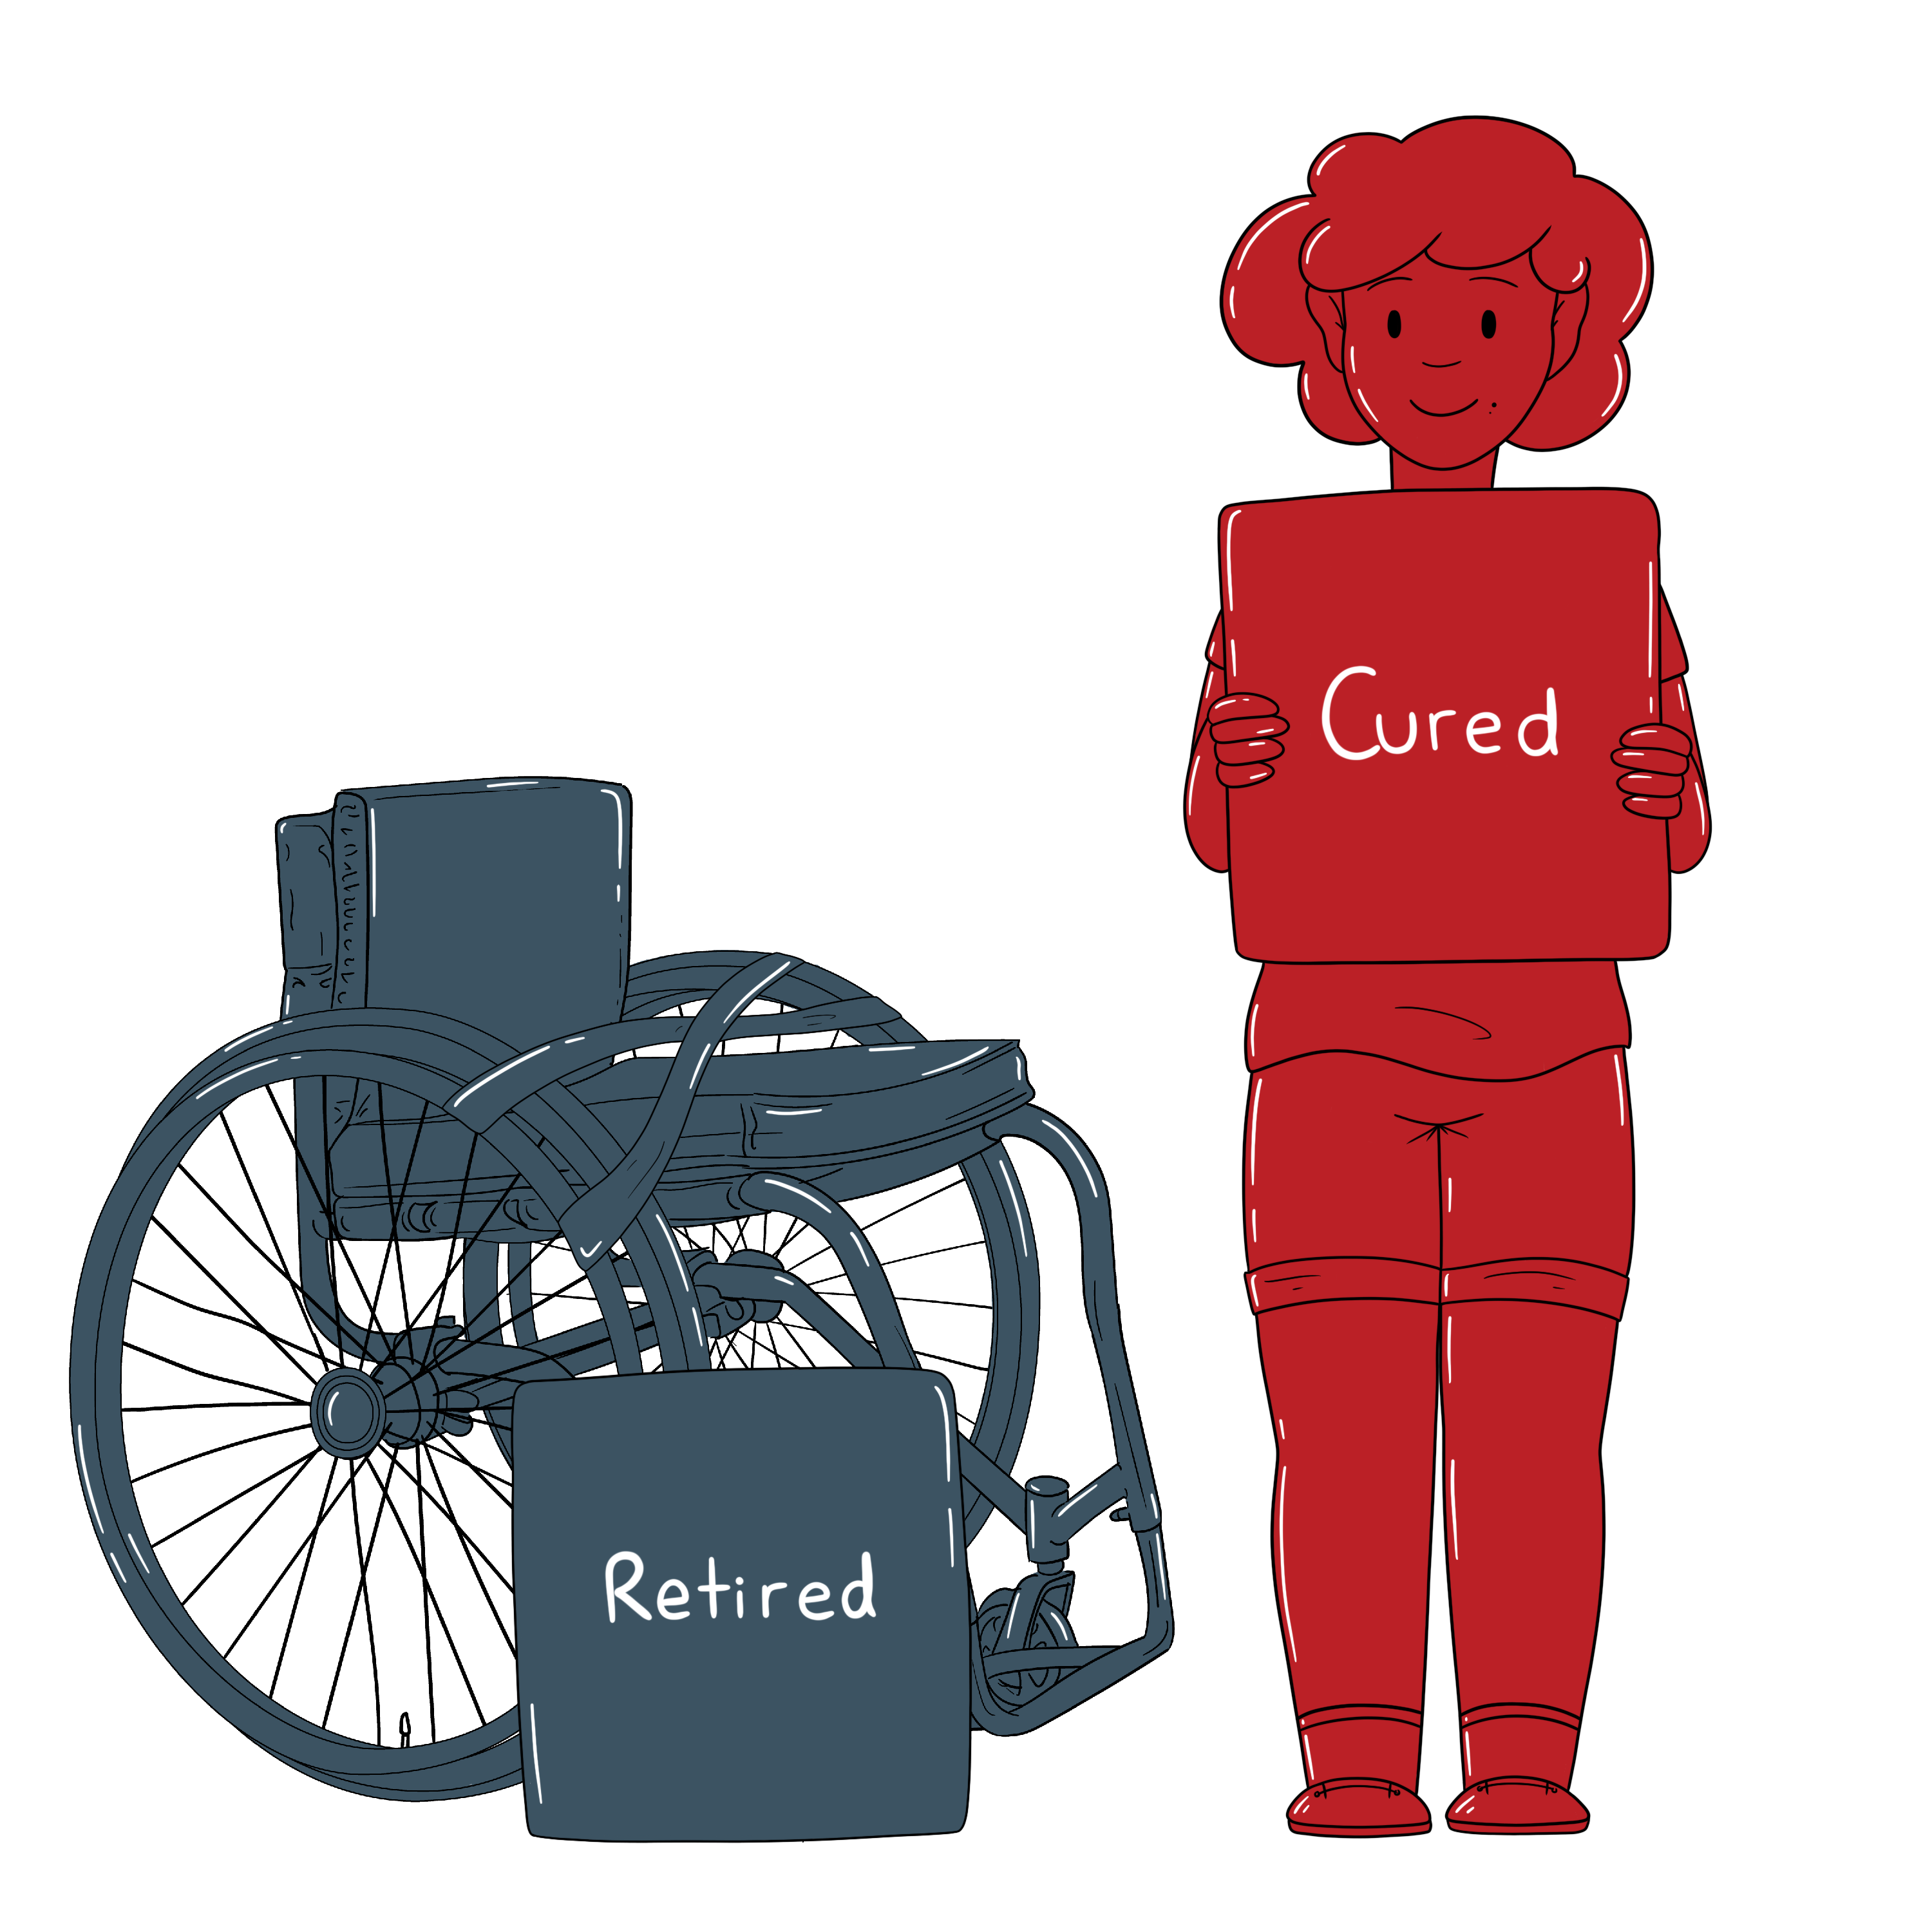

There have been multiple press releases about how adult stem cells have ‘cured’ a variety of ills, including spinal cord injury. As things stand, this is simply untrue for SCI. It is therefore vital that research continues using a multitude of cell types until solutions are uncovered.